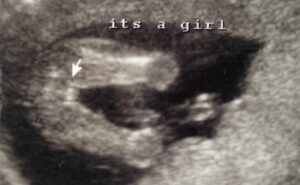

وفيما يلي بعض صور السونار التي يمكن ان تساعدك على التفرقه بين الاجنة الذكور والاناث في تصوير السونار.